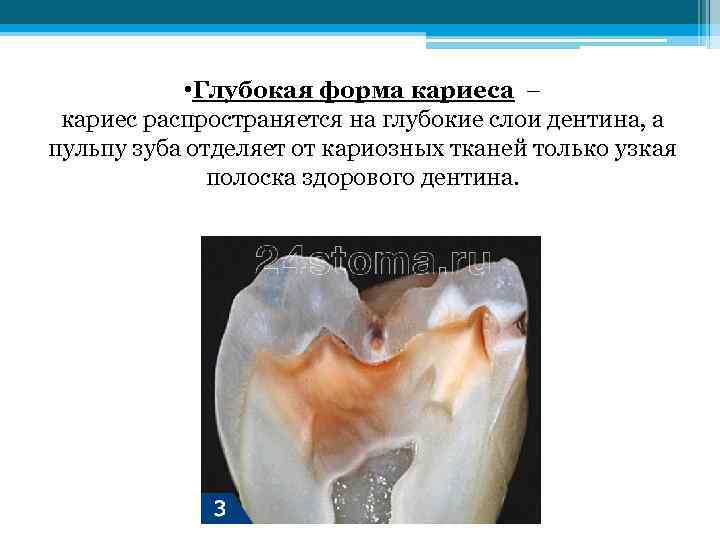

• Глубокая форма кариеса – кариес распространяется на глубокие слои дентина, а пульпу зуба отделяет от кариозных тканей только узкая полоска здорового дентина.

• Глубокая форма кариеса – кариес распространяется на глубокие слои дентина, а пульпу зуба отделяет от кариозных тканей только узкая полоска здорового дентина.